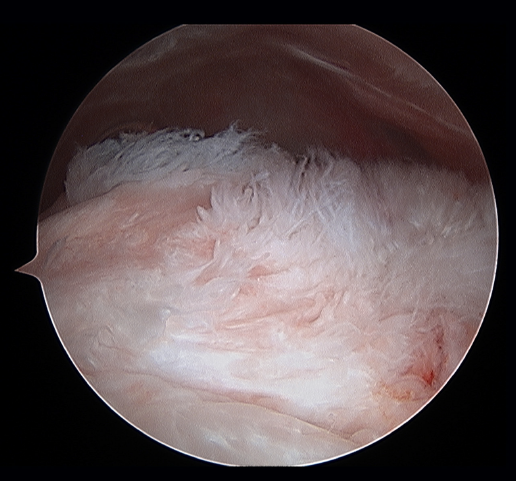

Traditionally, the appearance of rotator cuff disease has been described as a progressive disorder that initially manifests as acute tendinitis, continues as tendinosis with tissue degeneration and partial ruptures, and ultimately results in full thickness rupture(6). The terms tendinitis and tendinosis represent different stages of tendinopathy. Tendinitis refers to acute or chronic pain associated by definition to inflammation, even if the histological studies show an absence or only minimal presence of inflammatory cells(7). Tendinosis in turn refers to degenerative disease with or without inflammation (Figure 1). Tendinopathy is the term used to describe a clinical condition characterized by pain and functional alteration of the tendons of the rotator cuff, without specification of the concrete causal mechanism involved(8).

Figure 1. Arthroscopic view from the posterior portal in a case of severe supraspinatus tendinosis of a left shoulder.